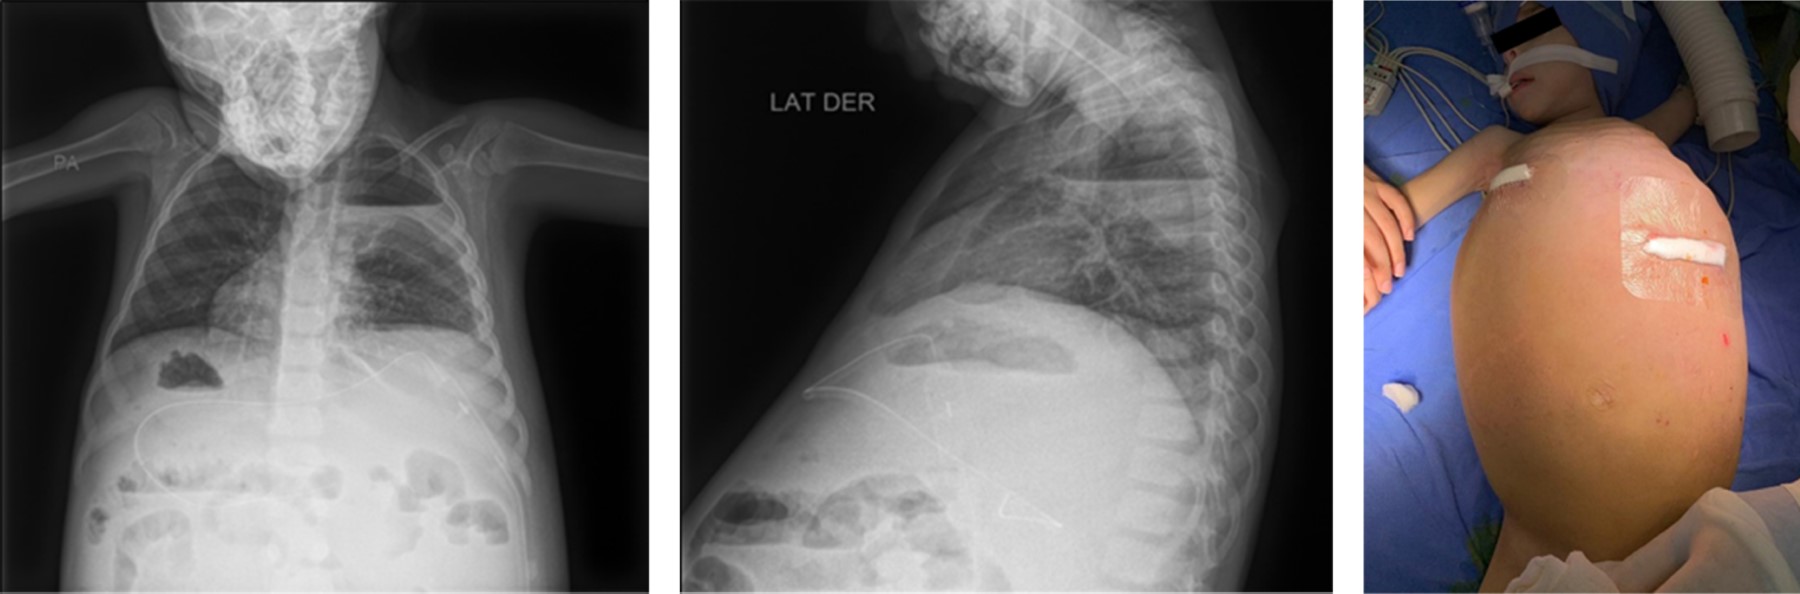

Primary intestinal lymphagiectasia in Klippel-Trénaunay syndrome. Anesthetic management. Case report

Klippel-Trénaunay syndrome with associated primary intestinal lymphangiectasia is a rare entity in pediatrics. It presents with edema due to hypoproteinemia, and in some cases with ascites. The objective is to present a clinical case whose diagnosis was certified by intestinal esdoscopy and biopsy. For refractary ascities, the treatment was surgical, performing peritoneal venous bypass. The anesthetic management of this type of patients has been described in limited reports, so in the present case we emphasize supportive therapy with albumin infusion as the proposed symptomatic treatment for patients with massive drainage of ascities.

Figure 1